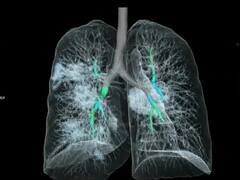

Lung Cancer

ধূমপান করেন না এমন ব্যক্তিদের মধ্যেই বাড়ছে ফুসফুসের ক্যান্সারের প্রকোপ, চিন্তার ভাঁজ ফেলছে এই সমীক্ষা

বিড়ি-সিগারেট না ছুঁয়েই ফুসফুসের ক্যান্সার ভারতীয়দের, নেপথ্য কারণ কী? জানালেন বিজ্ঞানীরা

ফুসফুসে ক্যান্সার ধরা পড়ে অত্যন্ত দেরিতে!অনেক সময়ই থাকে না লক্ষণ, কীভাবে এড়াবেন মৃত্যু?